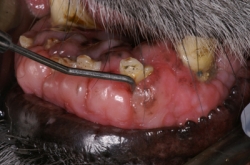

En el caso de la gingivitis, se clasifica según el tejido presente como “Gingivitis simple” en la cual la encía libre y papilar se encuentra hiperémica y sangrante; “Gingivitis hiperplásica” cuando la encía se encuentra con un aumento muy considerable en su tamaño y presenta un tejido inflamatorio hiperémico, sangrante e hiperplásico; y “Gingivitis hiperplásica fibrosa” cuando la encía está muy aumentada de tamaño y con una gran cantidad de tejido fibroso que se caracteriza por no ser hiperémico ni sangrante, sino que es de color rosa muy claro e inclusive hasta blanco y muy duro. Una de las características de las gingivitis hiperplásica y la gingivitis hiperplásica fibrosa es la presencia de bolsas periodontales falsas, ya que al medir la profundidad del surco este aparece aumentado, pero es debido al aumento del tamaño de la encía libre y papilar y no a la perdida de estructura ósea alveolar.

Haz CLICK sobre la imagen para ver descripción.